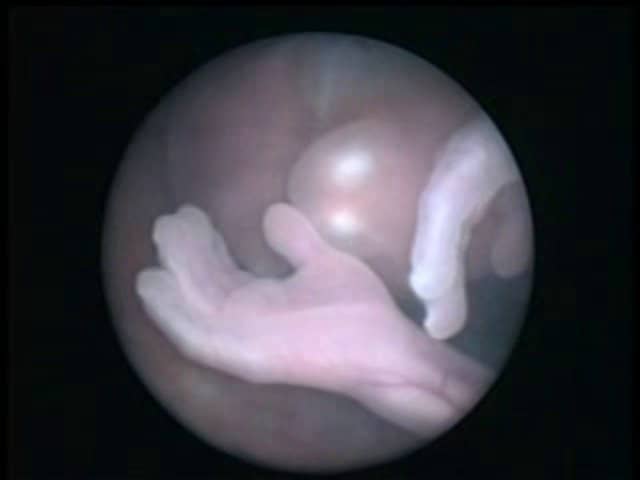

Ecografia Semana 21 De Embarazo En Alta Definicion High Definition Ultrasound 21 Weeks Youtube

Video De Ecografia 5d De 21 Semanas De Gestacion Ecox Youtube